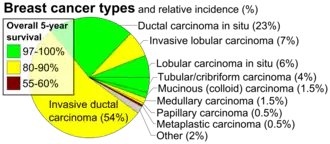

- Carcinoma in situ. This group constitutes about 15-30% of breast biopsies, more so in countries with high coverage of breast screening programs.[6] These have favorable prognosis, with 5-year survival rates of 97-99%.[7]

- Invasive carcinoma. This group constitutes the other 70-85%.[6] The most common type in this group is invasive ductal carcinoma, representing about 80% of invasive carcinomas.[6] In the US, 55% of breast cancers are invasive ductal carcinoma.[8] Invasive lobular carcinoma represent about 10% of invasive carcinomas,[6] and 5% of all breast cancers in the US.[8] The overall 5-year survival rate for both invasive ductal carcinoma and invasive lobular carcinoma was approximately 85% in 2003.[9] Ductal carcinoma in situ, on the other hand, is in itself harmless, although if untreated approximately 60% of these low-grade DCIS lesions will become invasive over the course of 40 years in follow-up.[10]

- ^ References for pie chart is located at Image description page in commons